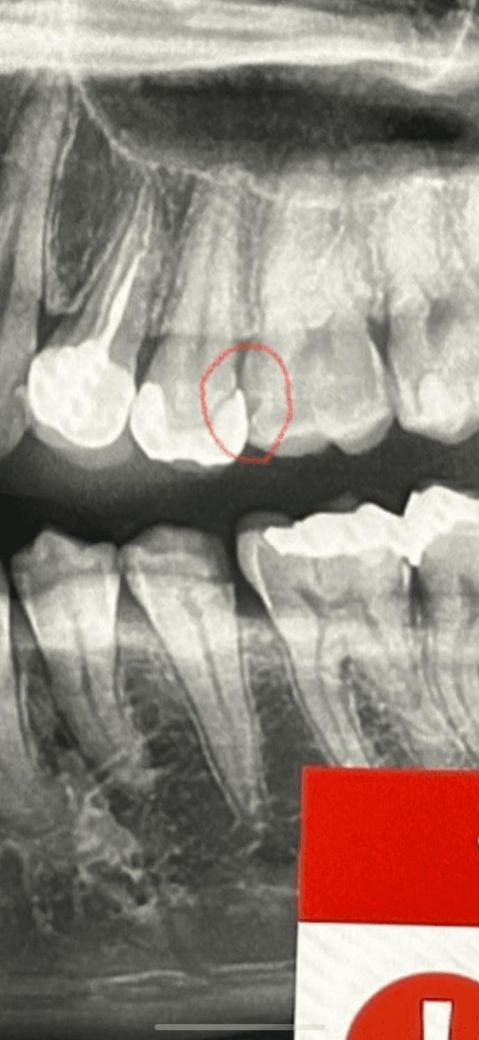

인접면 충치치료 어떻게 해야할까요?

26번치아 인접면 충치인걸로 보이는데 인레이 해야할 것 같다고 진단 받은 상태입니다.

• 1번 째 사진

사진상에 저정도 인접면 충치라면 레진보다는 인레이 치료를 하시는게 좋을것같습니다. 요즘에는 골드 보다는 치아색 나는 재료를 많이 사용합니다.

범위는 아주 크진 않은데 접근이 어려워서 위에서부터 뚫고 내려가야 할 것 같습니다. 그렇게 되면 충치보다 떼우는 양이 더 커지죠.

원한다면 레진으로 떼울 순 있으나 인레이보다 덜 정교하여 음식물이 잘 낄 수 있습니다.